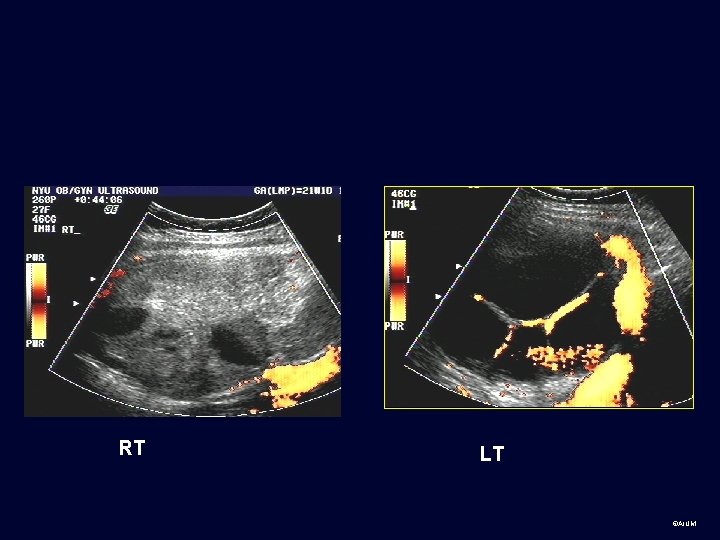

©AIUM

RT LT ©AIUM